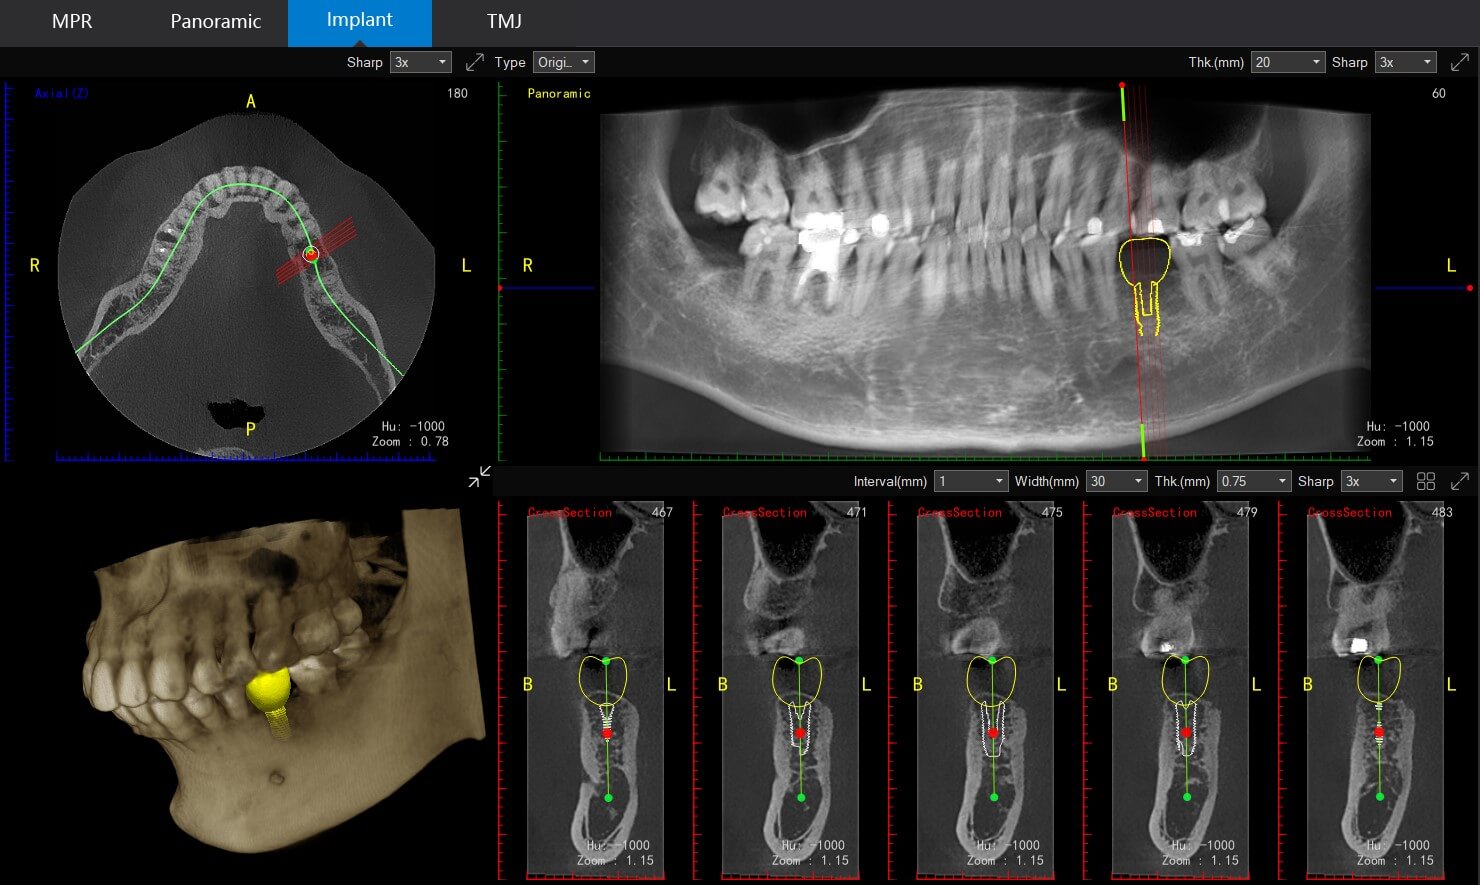

3-Dimensional (3D) Cone Beam CT scan

Our 3D Cone Beam CT scan offers a comprehensive view of your dental anatomy, providing a more in-depth analysis than conventional 2D X-rays. This advanced imaging technique is invaluable for complex cases, such as dental implant planning, root canal treatment, and assessing jawbone structure.

Enhanced Treatment Planning

The 3D CBCT scans give our dentists a comprehensive view of your oral structures, enabling them to plan complex procedures with greater precision and accuracy.